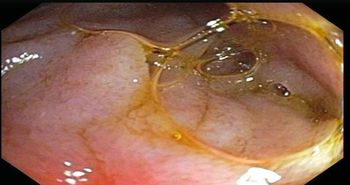

These endoscopic findings help explain worsening dysphagia in a 32-year-old man. Esophageal biopsies prove positive for eosinophilia. How would you proceed?

What would your diagnosis be in this young man and how would that inform your next step?